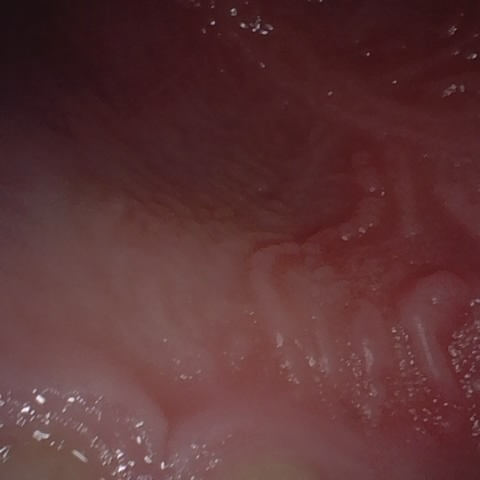

Annotated as "Good"